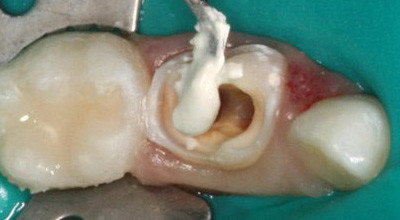

Abb. 1: Karies profunda an Zahn 74. Abb. 2: Zustand nach Kariesexkavation.

Abb. 3: Pulpaamputation. Abb. 4: Reinigung des Pulpakavums.

Abb. 5: Sicht auf das Pulpakavum mit Amputationsstellen der Wurzelpulpa. Abb. 6: Portland-Zement wird in das Pulpakavum eingebracht.